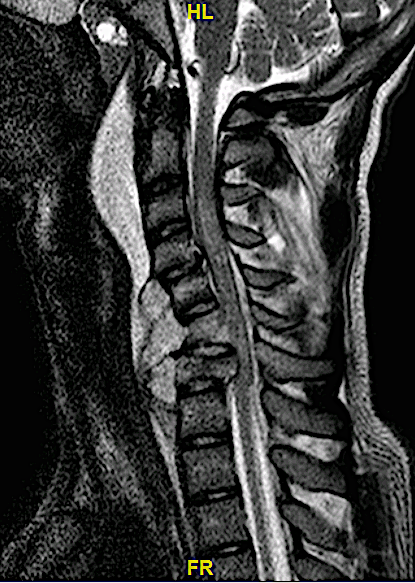

El adolescente fue rescatado inconsciente tras precipitarse («tirarse de cabeza») al agua».

Obsérvese el hematoma prevertebral, la cifosis segmentaria y la afectación vertebral C4, C6 y C7.

El paciente presentaba tetraplejia nivel C4.